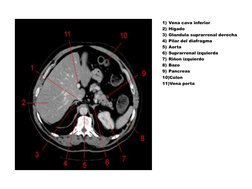

1) Vena cava inferior

2) Higado

3) Glandula suprarrenal derecha

4) Pilar del diafragma

5) Aorta

6) Suprarrenal izquierda

7) Rion izquierdo

8) Bazo

9) Pancreas

10)Colon

11)Vena porta